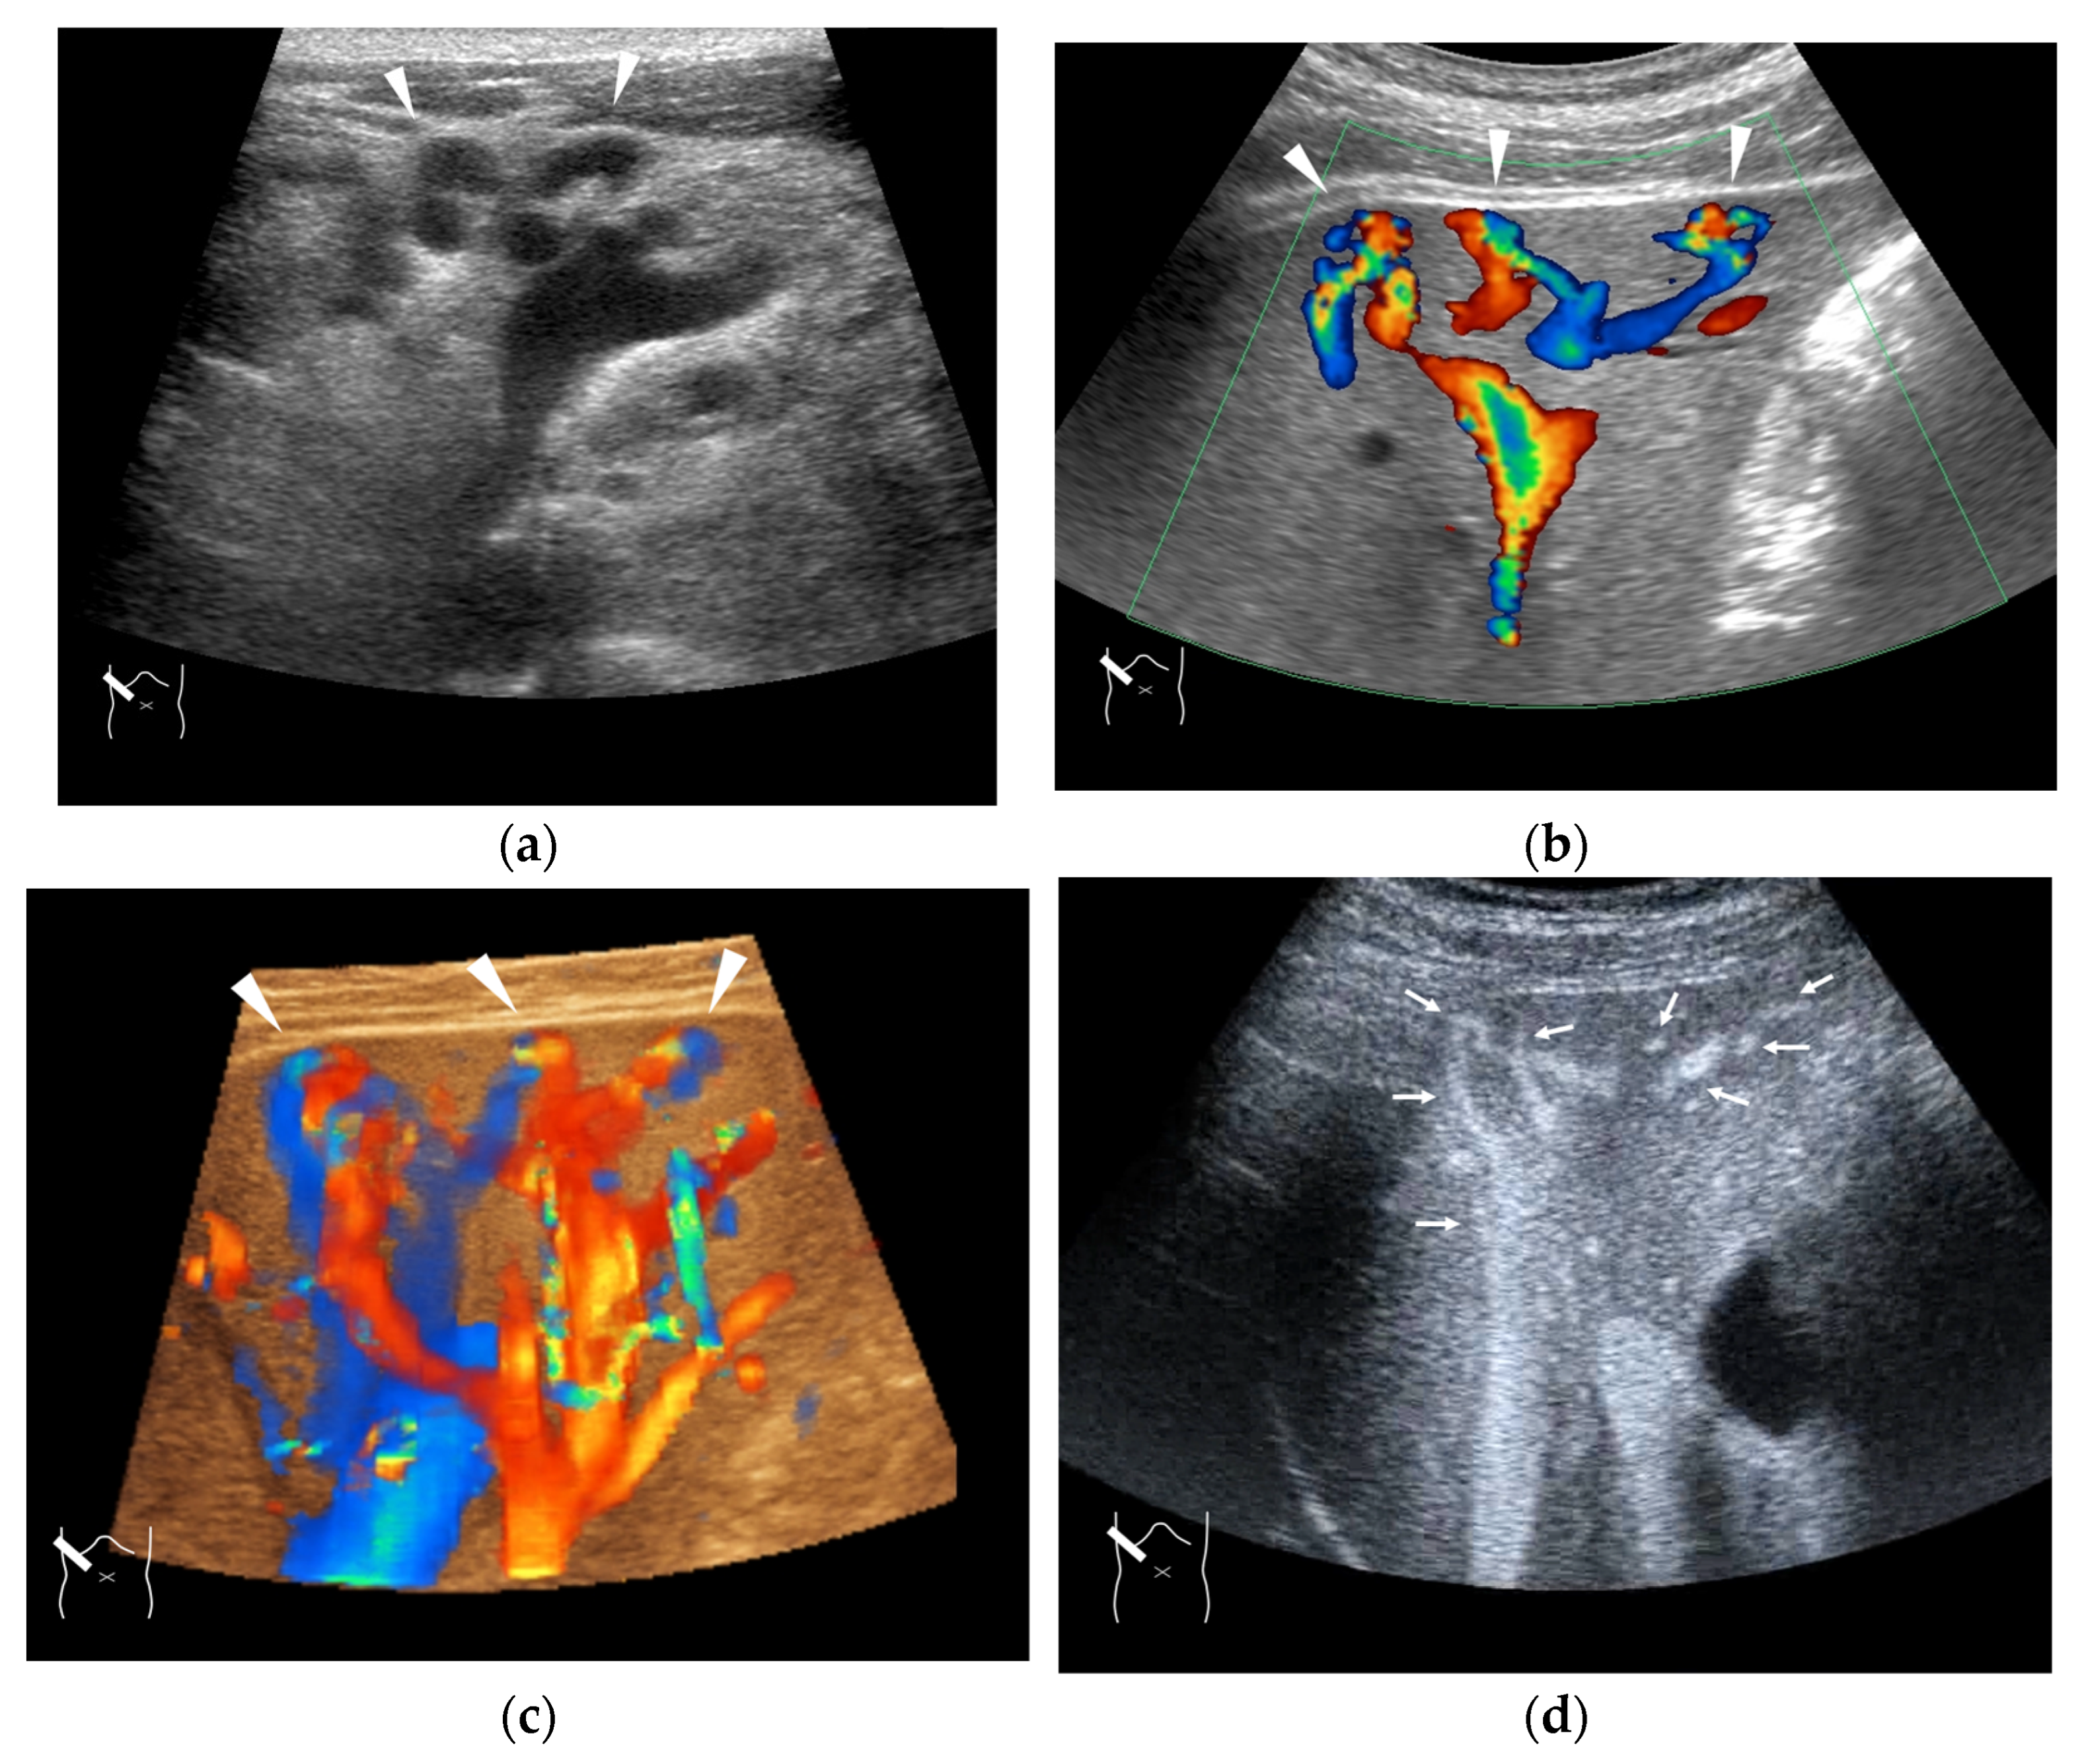

4.1. HHT-Related HV Abnormalities

- Naganuma, H.; Ishida, H.; Kuroda, H.; Suzuki, Y.; Ogawa, M. Hereditary hemorrhagic telangiectasia: How to efficiently detect hepatic abnormalities using ultrasonography. J. Med. Ultrason. 2020, 47, 421–433. [Google Scholar] [CrossRef]

- Schelker, R.C.; Barreiros, A.P.; Hart, C. Macro-and microcirculation patterns of intrahepatic blood flow changes in patients with hereditary hemorrhagic telangiectasia. World J. Gastroenterol. 2017, 23, 486–495. [Google Scholar] [CrossRef]